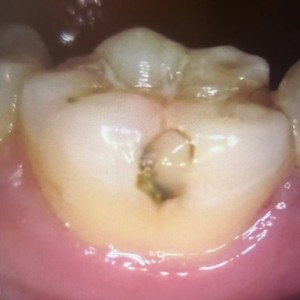

1日目 プラスチックを除去し、虫歯の部位を染める「うしょく検知液」で染色ながら虫歯を取り除いていきました。型取りを行い仮の材料を充填しました。

2日目 出来上がってきたセラミックを接着性セメントで装着しました。